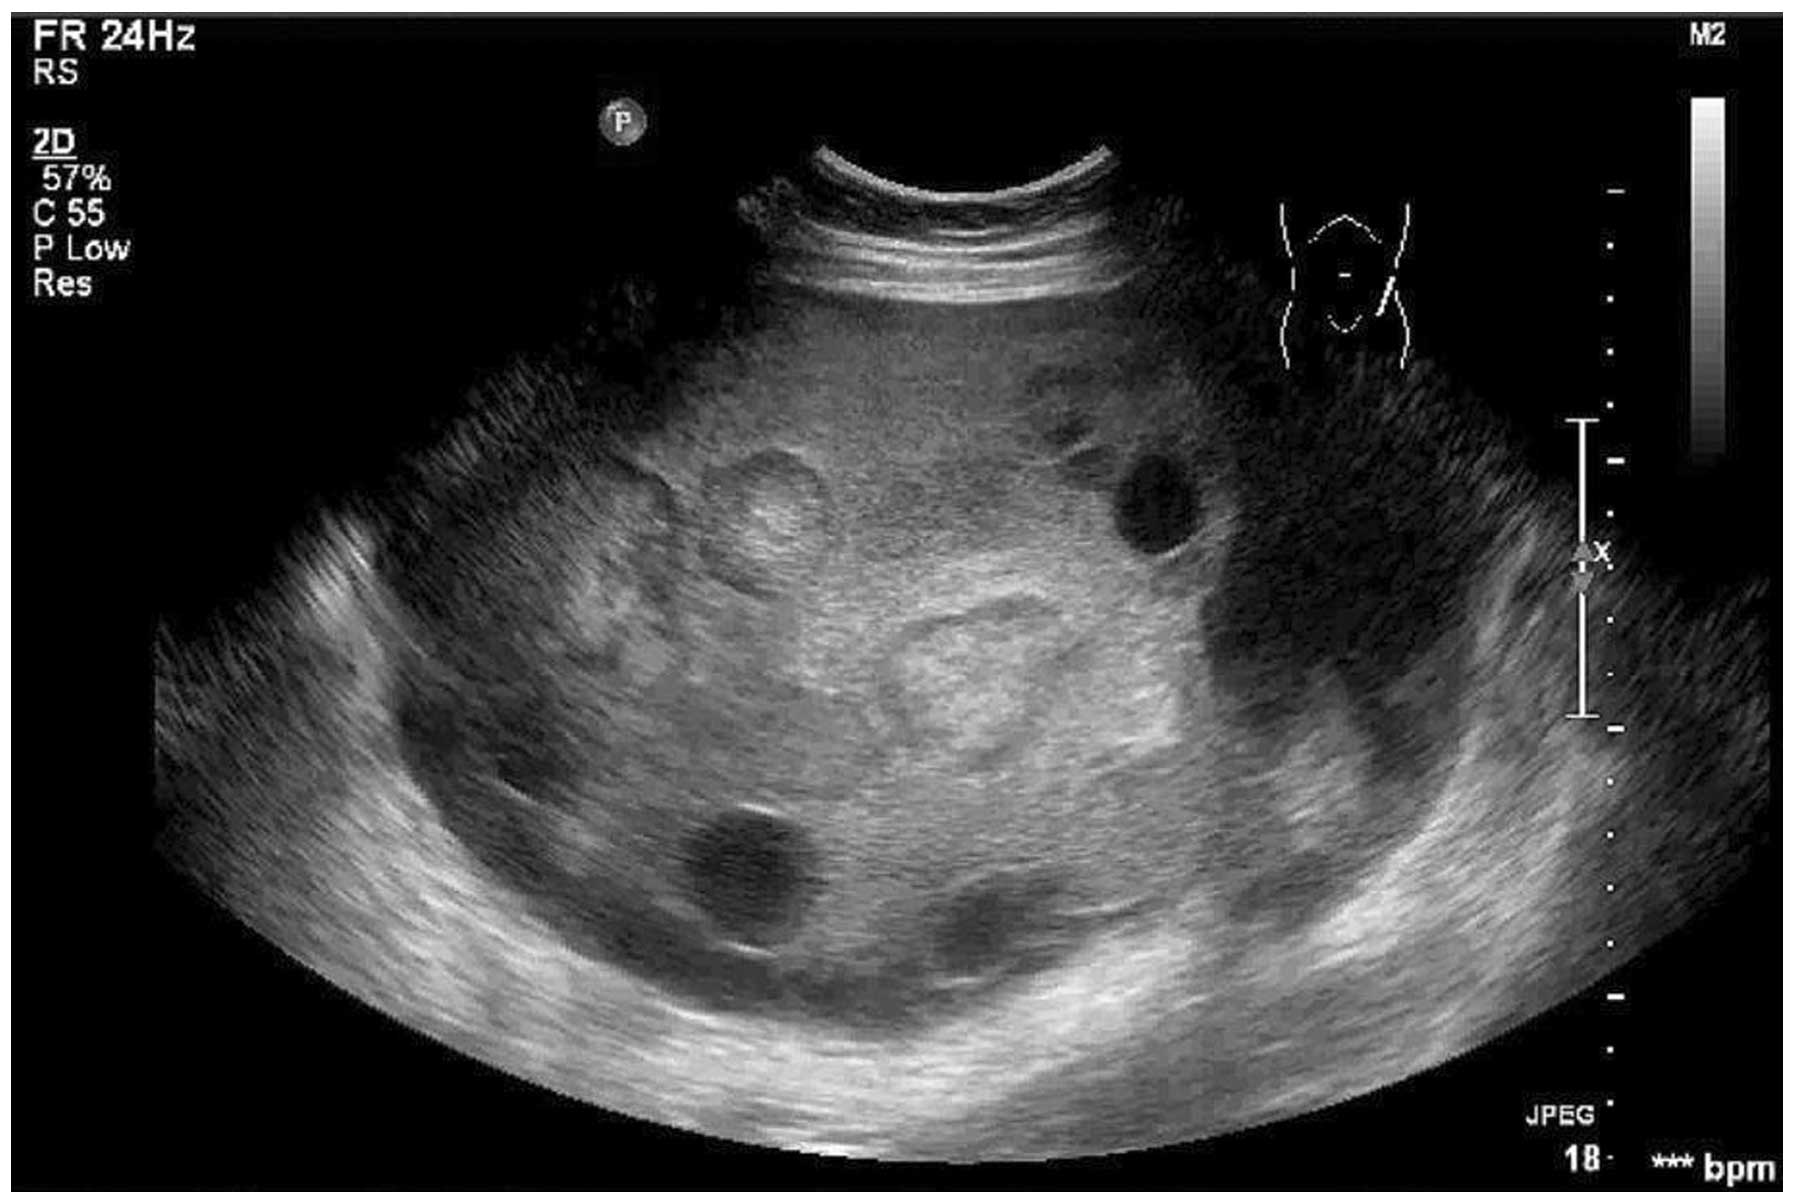

Preeclampsia is often diagnosed during routine prenatal appointments, when your healthcare provider checks your weight gain, blood pressure and urine protein. If preeclampsia is suspected, additional blood tests may be ordered. In some cases, blood pressure readings will be observed in the hospital and a 24-hour urine collection is performed to check for proteinuria (protein in the urine). An ultrasound and fetal monitoring may also be used to provide more information about the baby.

Severe preeclampsia may require that you be hospitalized . In the hospital, your doctor may perform regular nonstress tests or biophysical profiles to monitor your baby's well-being and measure the volume of amniotic fluid. A lack of amniotic fluid is a sign of poor blood supply to the baby.